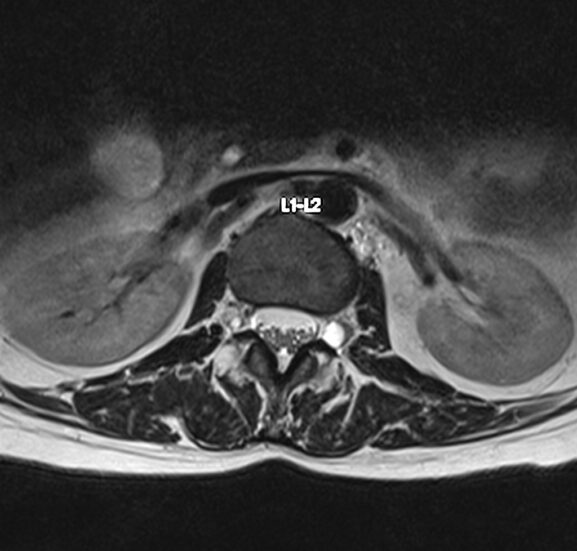

Resonancia Magnética de columna lumbar

“QUISTES PERINEURALES”

Los quistes perineurales son quistes llenos de líquido cefalorraquídeo en las raíces nerviosas, localizados principalmente en la zona sacra de la columna vertebral, aunque pueden encontrarse en cualquier sección de la columna vertebral; pueden causar una radiculopatía progresivamente dolorosa. Las mujeres se ven afectadas con mayor frecuencia que los hombres. Los pacientes con quistes perineurales presentan dolor en la zona de los nervios afectados por el quiste, debilidad muscular, dificultad para sentarse durante periodos prolongados, pérdida de la sensibilidad, pérdida de reflejos, dolor al estornudar o toser, inflamación en la zona sacra, parestesias, dolor de cabeza, ciática, y disfunción intestinal, de vejiga y sexual.

El diagnóstico se basa en la resonancia magnética.